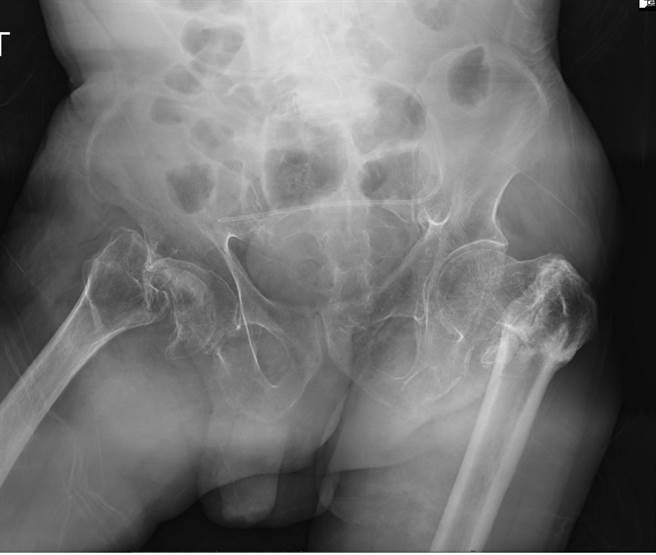

台中大里仁爱医院骨科医师黄赞文指出,该名78岁患者3年多前因为癫痫发作后跌倒,双侧的髋关节因此疼痛需要用助行器辅助,加上疫情关系不敢就医,两脚肌肉变得萎缩无力而不断跌倒,后来只能用轮椅协助度日,3个月前因为再次癫痫发作送到大里仁爱医院急诊室,经X光检查才发现双侧的髋关节已经骨折变形多时且有严重髋关节炎。

黄赞文说,高龄长者因感觉统合能力降低、肌肉萎缩、平衡感变差,再加上本身如有癫痫、失智或是视力变差和使用安眠镇静药物都容易跌倒进而造成骨折。许多家属认为长辈年纪大开刀风险高希望不要手术,通常上肢骨折可以用石膏固定的方式来治疗,但在髋部骨折最好的治疗方式仍是尽早进行手术。

他解释,由健保资料库的资料分析,75岁以上的国人髋部骨折风险会大幅增加,髋部骨折若没有积极治疗很容易造成不断跌倒与骨折的恶性循环,台湾女性髋部骨折病患在一年内的死亡率为15%,而男性更高达22%。